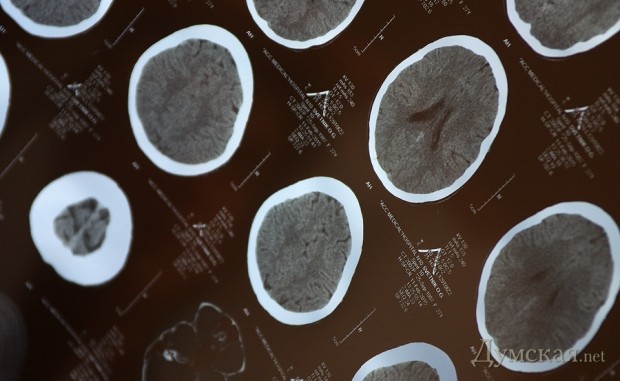

«ДТП произошло на углу Бунина и Александровского проспекта. Было около 9 часов утра. Я переходила перекресток по переходу и точно на зеленый свет, никуда не опаздывала, — вспоминает девушка. — На этом перекрестке — постоянные пробки. Я прошла те две полосы, которые ведут в сторону моря, потом заглянула на третью, поскольку крайней в пробке стояла маршрутка, и машины, идущие по встречке, могли меня не видеть. Там никого не было, и я пошла дальше. И в этот момент на меня сзади наезжает полосатый сине-белый автобус. Как он на меня ехал я, естественно, не видела, и заметила его только в последний момент. Еще подумала: «Не может этого быть! Откуда он тут взялся?». От удара девушку отбросило примерно на метр, она довольно сильно ударилась об асфальт головой и копчиком. «События, которые были дальше, я помню очень смутно, — признается Ольга. — Из маршрутки вышел водитель, и посадил меня на переднее сидение. Я ему зачем-то пыталась объяснить, что мне надо на работу, но он убедил меня, что мне надо в поликлинику, причем почему-то именно в двадцатую, что на Таирова. Вот мы едем. Я то прихожу в себя, то отключаюсь. Маршрутка тем временем куда-то едет. В итоге я понимаю, что в салоне полно народу. Одни выходят, другие заходят. Все постоянно пытаются передать через меня оплату за проезд, обижаются, что я не понимаю, чего они хотят». Пострадавшая начала приходить в себя и почувствовала боль в теле по дороге на Таирова: «Проезжаем мимо больницы. Я пытаюсь объяснить, что, мол, вот же она, но водитель говорит, что ему надо сначала на конечную. На конечной, когда все люди выходят, он пытается скормить мне какие-то таблетки «от головы». Я настаиваю, что мне надо в больницу. Он, вроде, соглашается, но теперь ему надо на заправку. Едем заправляться. После заправки он снова возвращается на конечную. Пытается мне дать каких-то денег. В итоге я беру у него номер телефона и иду в поликлинику сама». В двадцатой поликлинике девушку встретили коллеги по работе: «В итоге к шести часам вечера я лежу в «Инто-Сане». Кормят тут на убой, пичкают таблетками. Просканировали голову, нашли какие-то темные бороздки. Еще невропатолог недоволен какими-то моими рефлексами. Но говорят, что жить буду», — заключила одесситка. Что же касается водителя маршрутки, то им сейчас занимаются правоохранители.Ольге уже показывали его фотографию для опознания, и она подтвердила, что это - тот водитель.